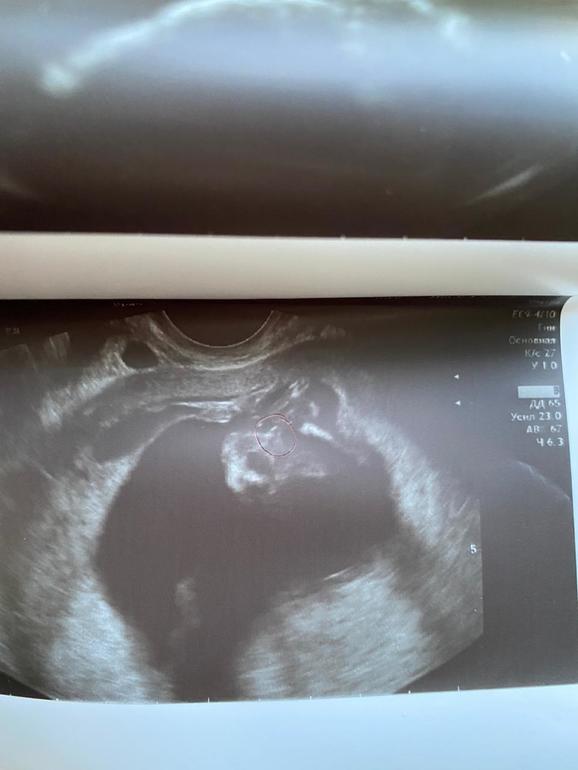

Пол малышаНа скрининге сказали девочка ходила сегодня говорят мальчик как так...посмотрите фото похоже на мальчика?

Пипирка обведена ручкой срок почти 15 недель.

Я б сказала, что фото очень неудачное, чтоб сказать точно , что это мальчик или девочка. Для парня в 14 недель уж больно достоинство большое, как у новорождённого, если не старше. Для девочки тем более. Да и на пуповину очень похоже. В общем, нужно третье мнение, как говорится)